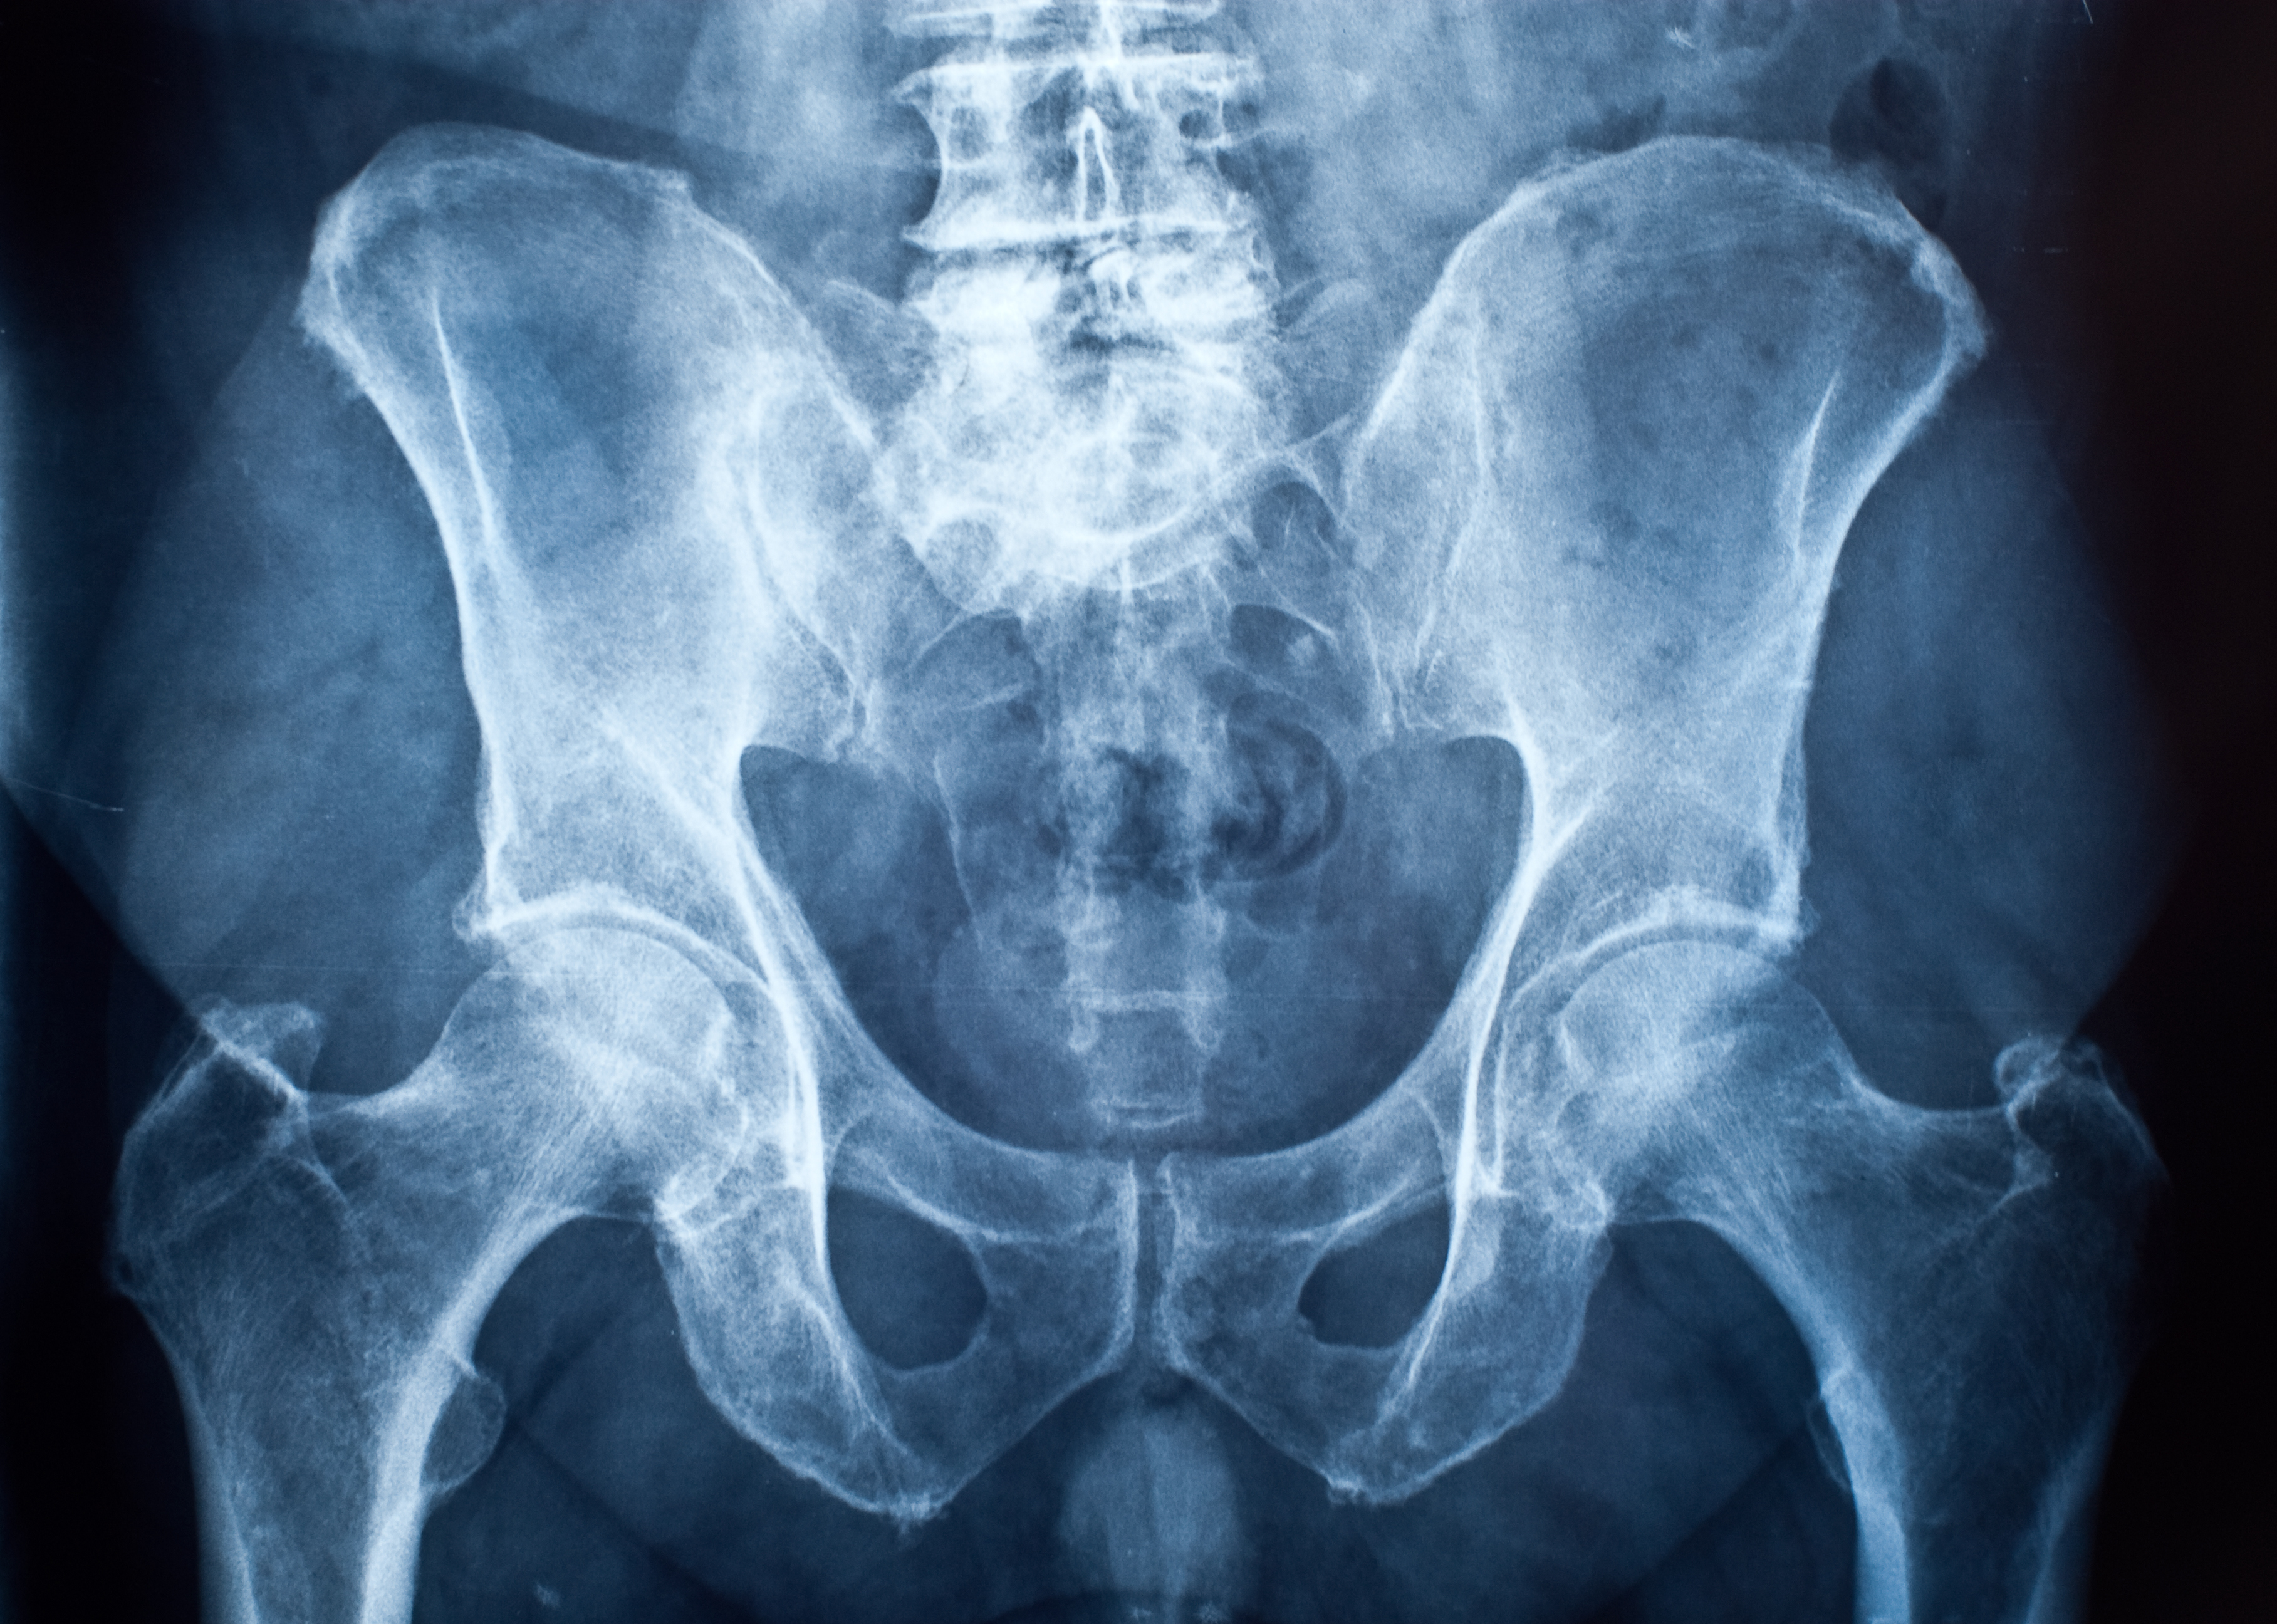

L’examen clinique montre des pieds normaux et des genoux axés. Une sensibilité est constatée à la mobilisation en rotation interne de la hanche, genou fléchi, mais sans provoquer la douleur ressentie en course. L’examen du rachis est sans particularité. Une radiographie du bassin de face en charge, des faux profils et des profils de Dunn sont demandés. En raison d’un échec du traitement antalgique de première intention, des anti-inflammatoires non stéroïdiens (AINS) et un opioïde faible sont prescrits pour une courte durée, avec prise à la demande en fonction de l’intensité de la douleur.

Radiographie de hanche normale